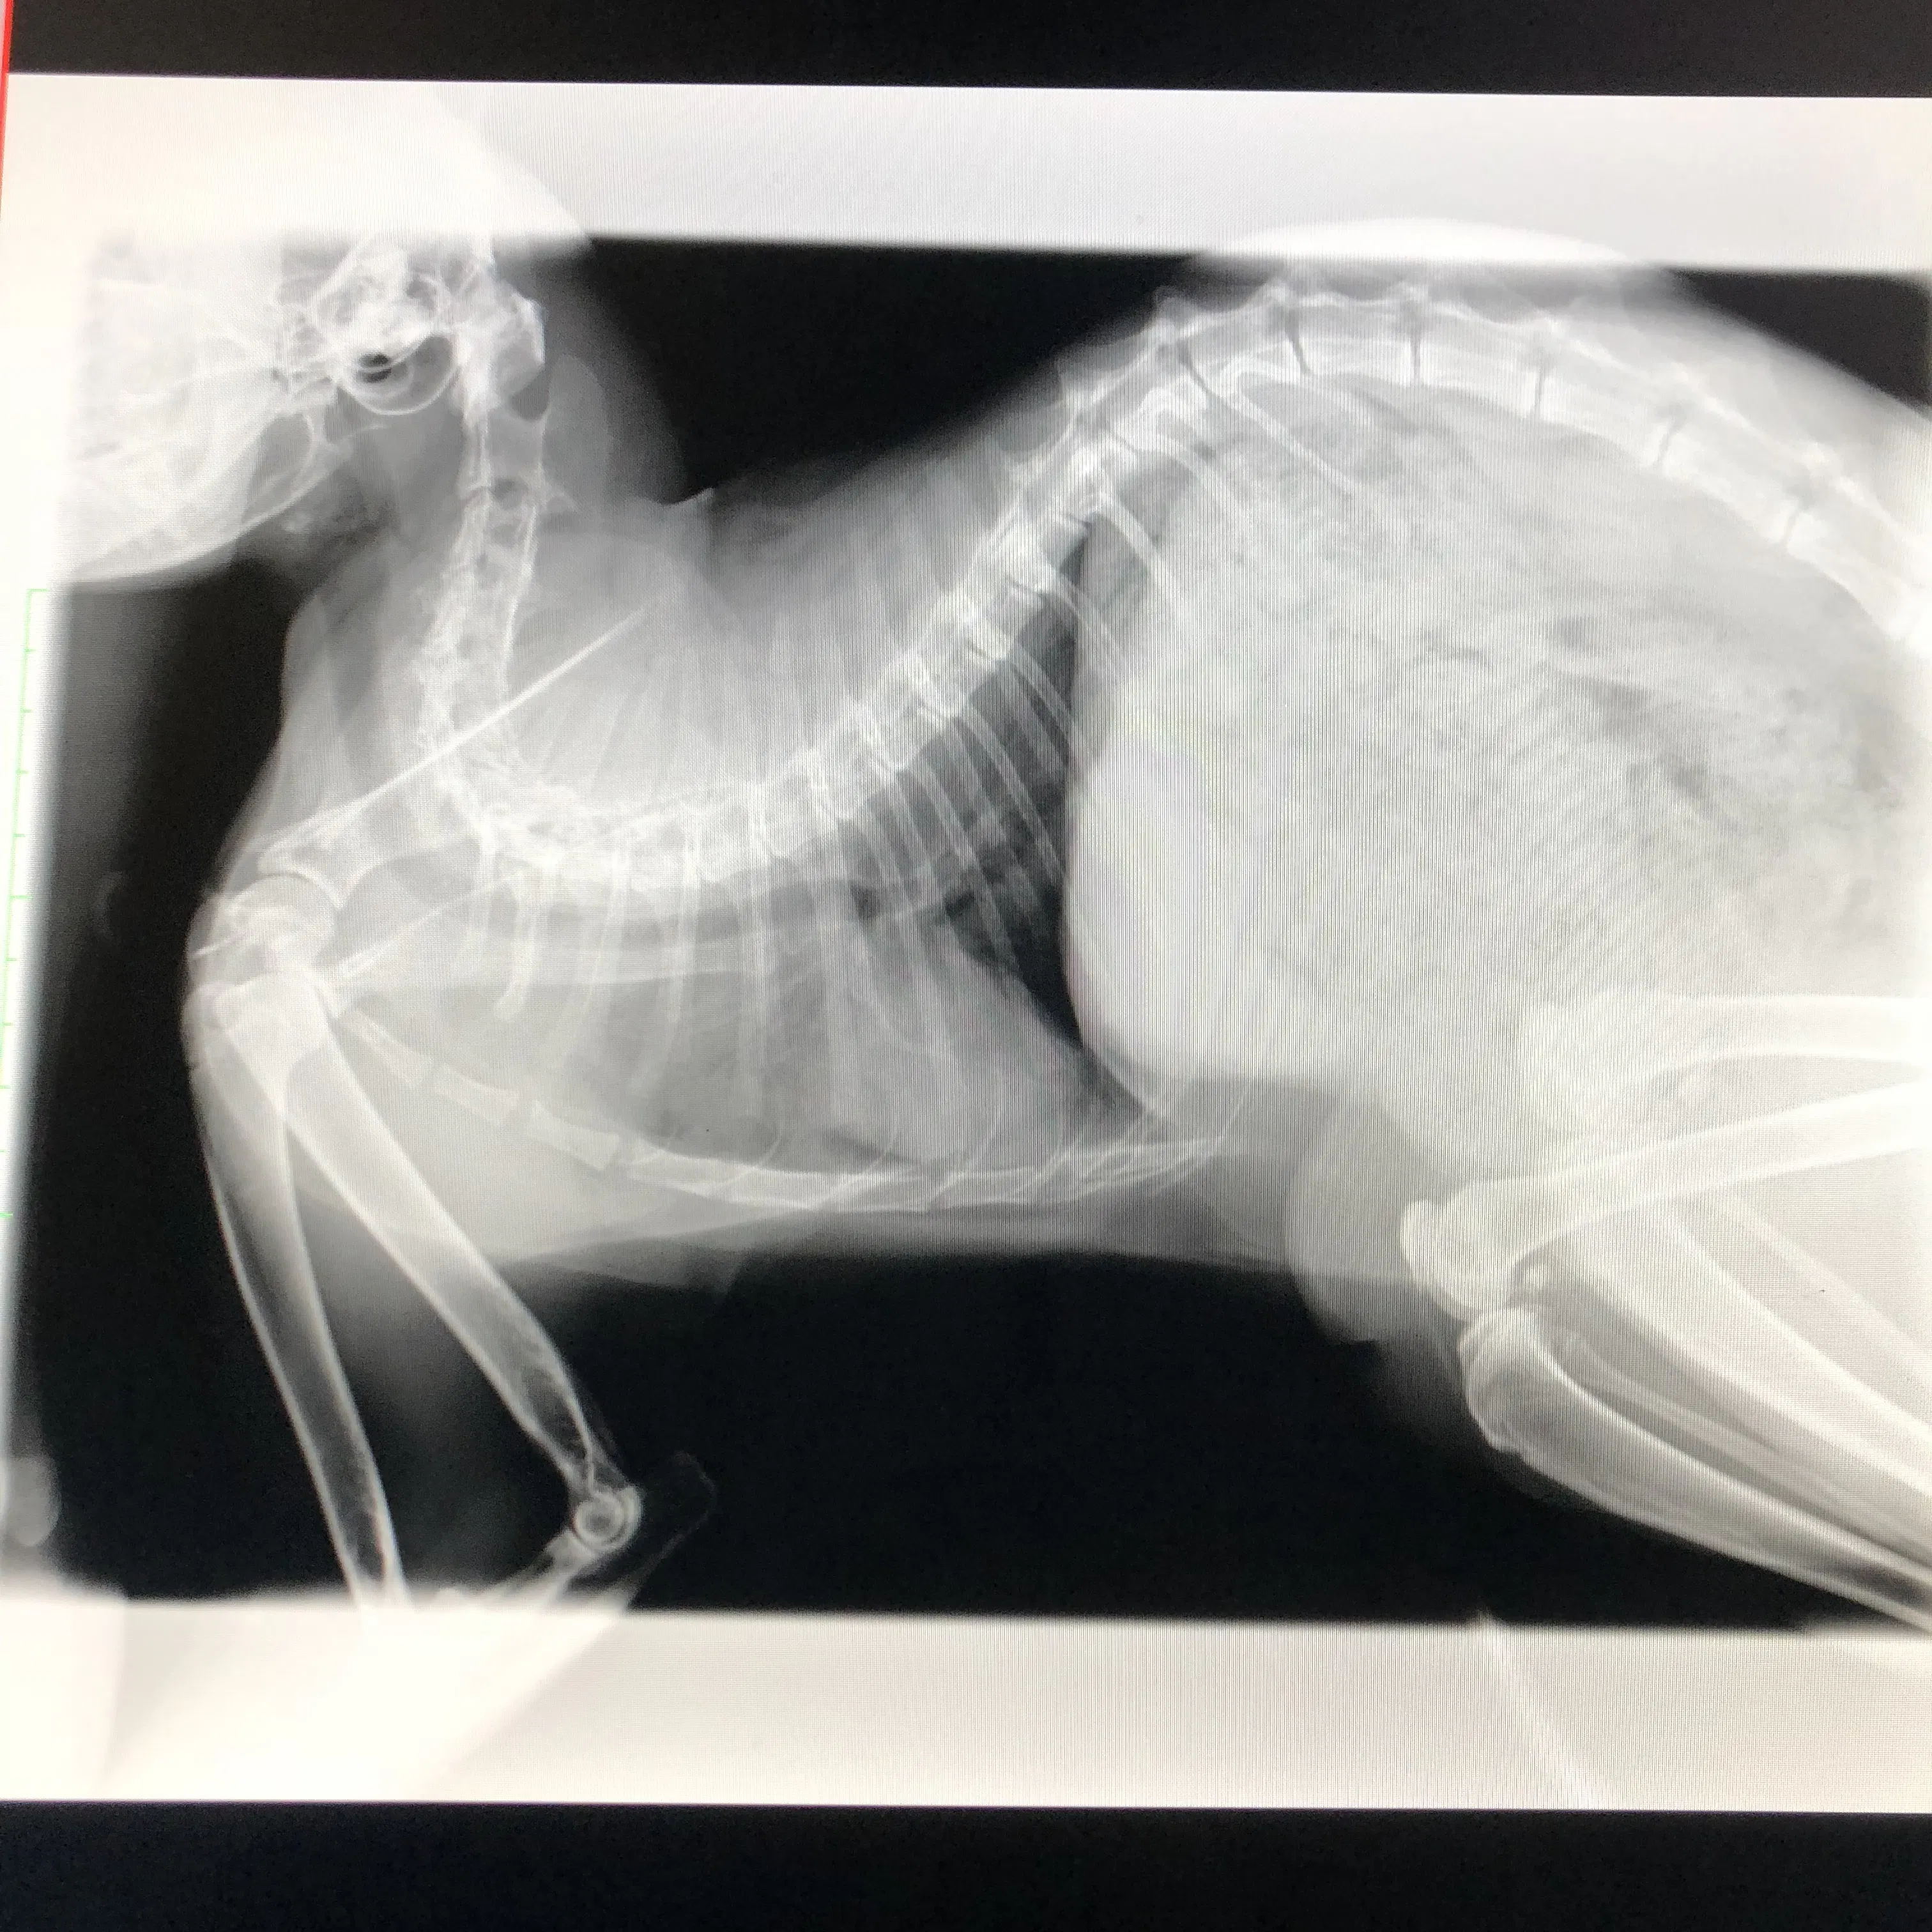

抗がん剤前のレントゲンです

胸の辺りが真っ白!

朝病院へ行き先週の抗がん剤の効果が出たのかを見ました、やはり効いています!真っ白だった胸部や肺の一部が改善していた!

実はレントゲンで効果がないと判断できたら抗がん剤は辞めて緩和治療に切り替えて行こうかとずっと悩んでいたので少し気持ちがスッとしました。

前回と違い腫瘍が小さくなりましたので今日は夕方までの半日入院だからカイちゃんのストレスも減りますね!